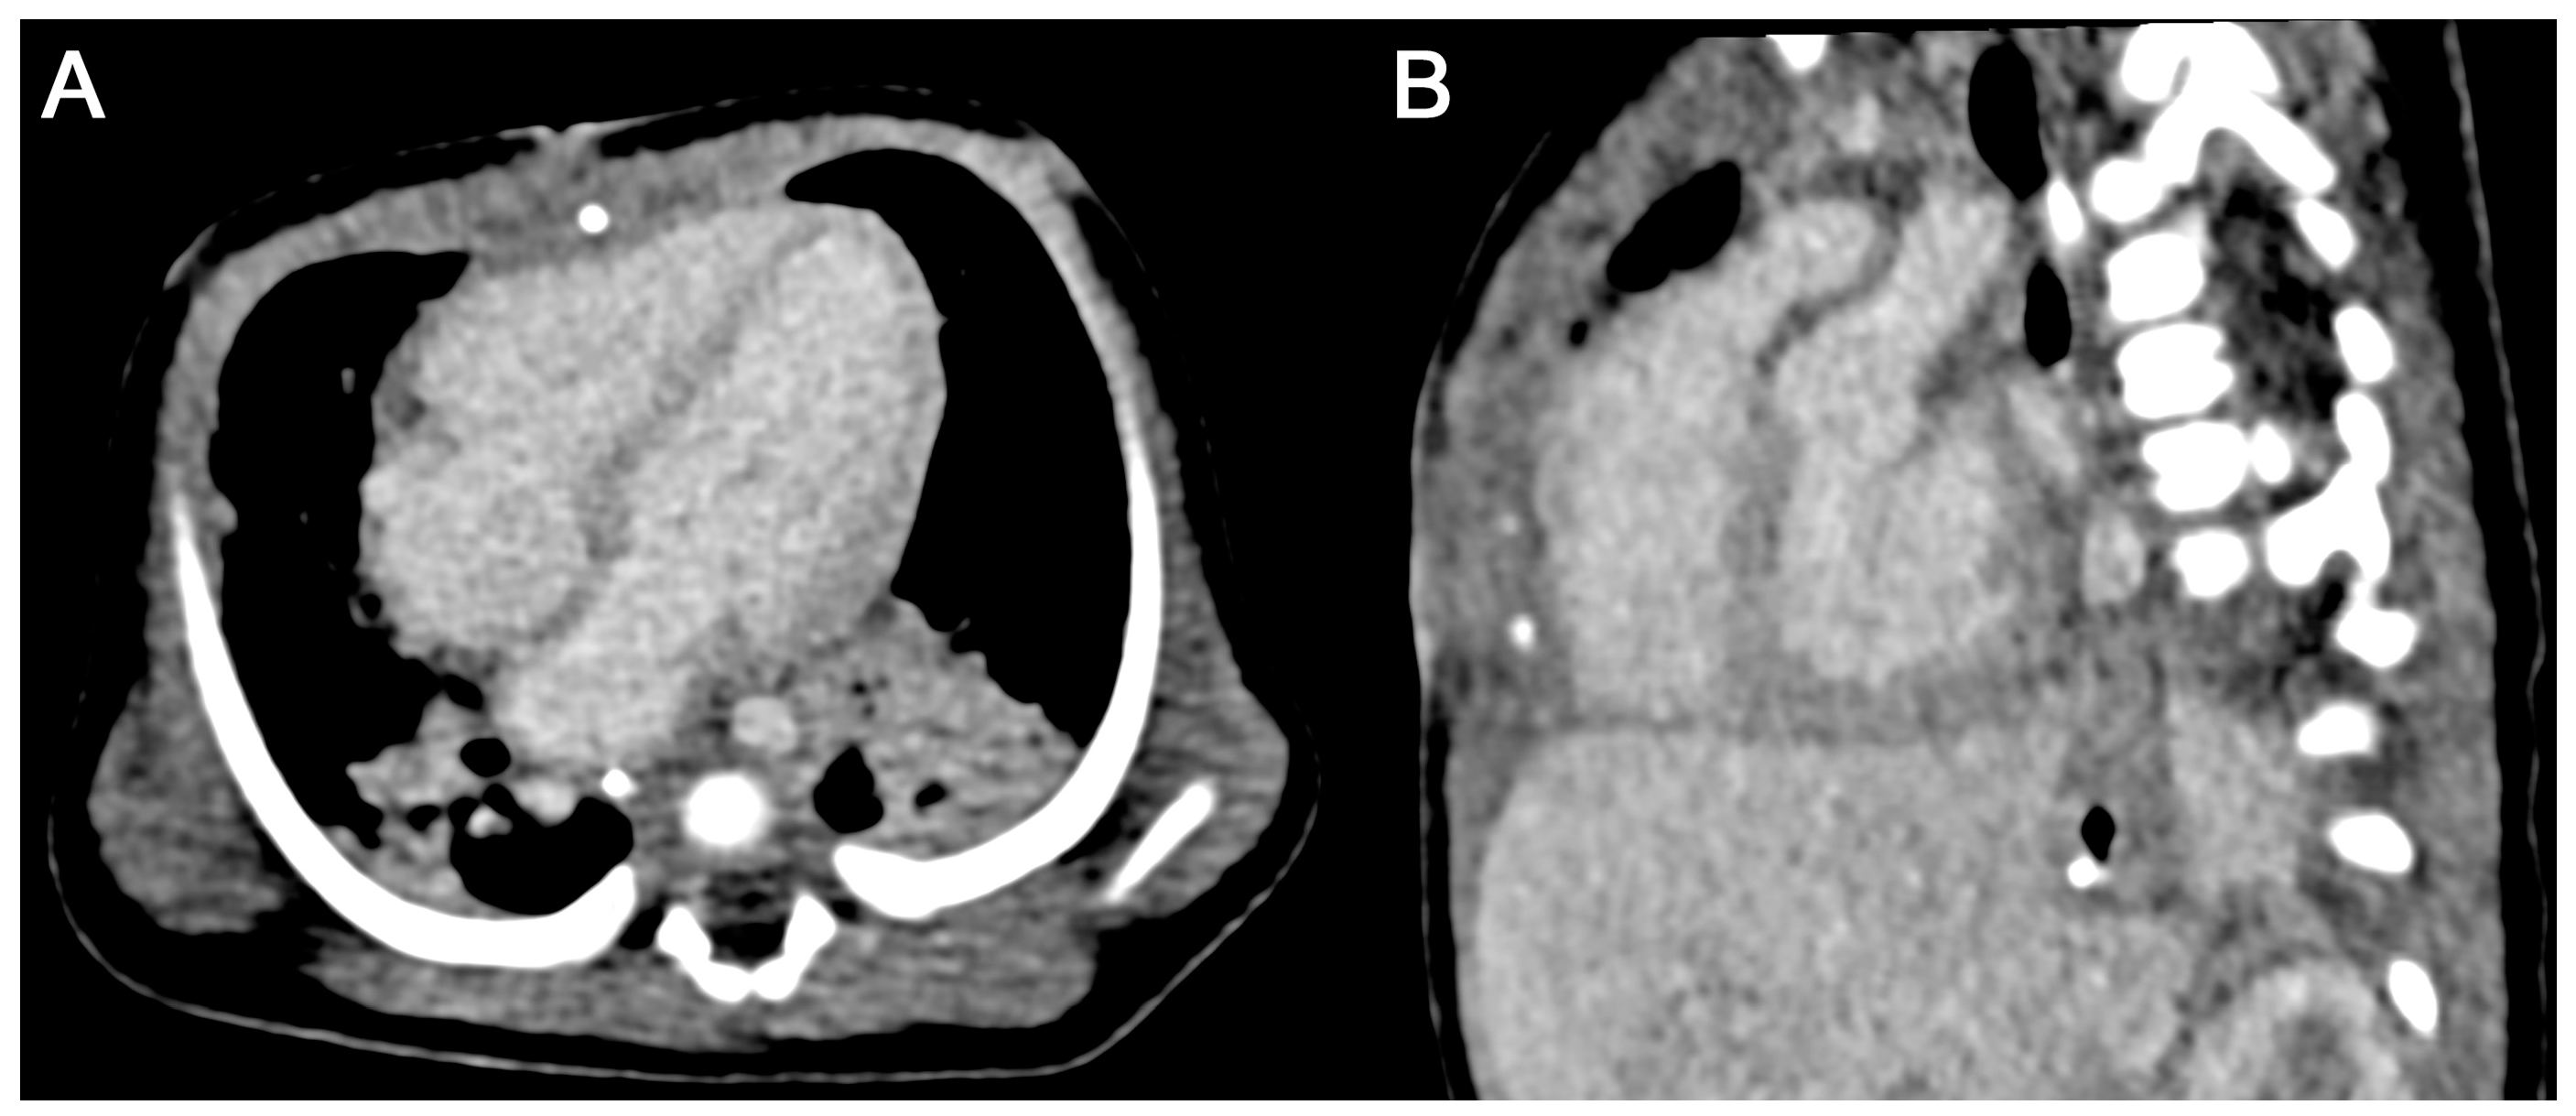

3.3.2. Subjective Image Quality